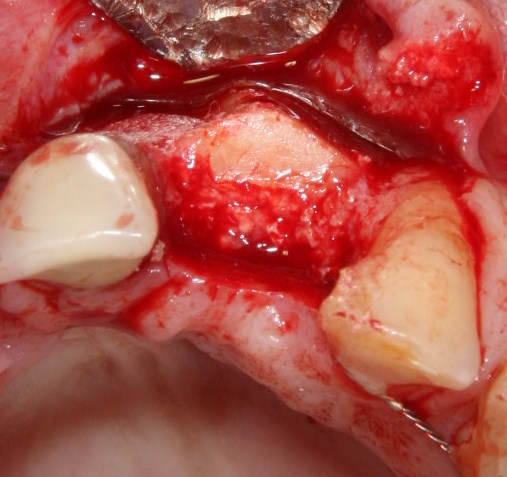

Делаем разрез в пределах кератинизированной десны. Скелетируем кость, видим следующее:

По краям от лунки видны остатки прошлых операций. Это не кость, а грануляции вперемежку с твердыми частичками биоматерила. Жди мы хоть несколько лет — вряд ли они организовались в приемлемую для имплантации костную ткань. Поэтому мы всё вычищаем, до естественной кости:

Ее объем, как мы видим, небольшой, использовать его для ПРАВИЛЬНОЙ установки импланта нереально. Почему выделил слово «ПРАВИЛЬНОЙ»? Потому что некоторые типы имплантационных систем позволяют установить имплантат хоть куда, хоть в какой объем кости, если очень хочется, конечно. Но ведь у нас нет задачи «воткнуть» имплантат всеми правдами и неправдами, верно? Комплексная цель лечения — воссоздание полноценно функционального зуба со всеми окружающими тканями. Чем мы, собственно, и занимаемся.